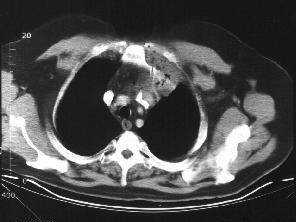

问题 中年男性,间断性腰背痛4个月,突发左下肢全肢水肿,小腿有张力性水泡,水肿累积会阴部,常规胸腹部CT扫描如图所示,你认为哪些征像及结论正确 ( )

选项 A、奇静脉变细 B、正常CT表现 C、下腔静脉变细 D、奇静脉增粗 E、下腔静脉缺如

答案 DE